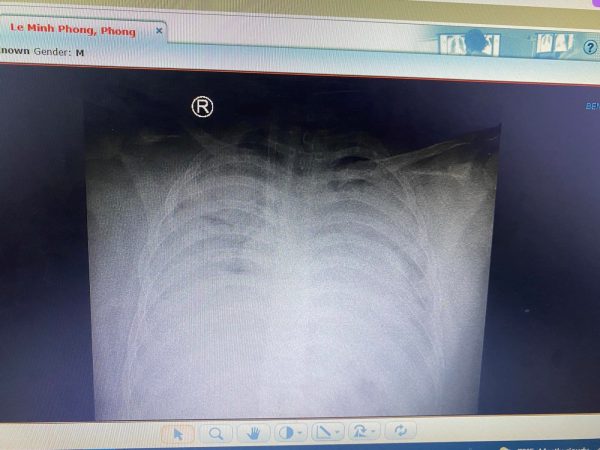

Xquang ngực cho thấy hình ảnh tổn thương thâm nhiễm phổi nặng lan tỏa 2 phế trường.